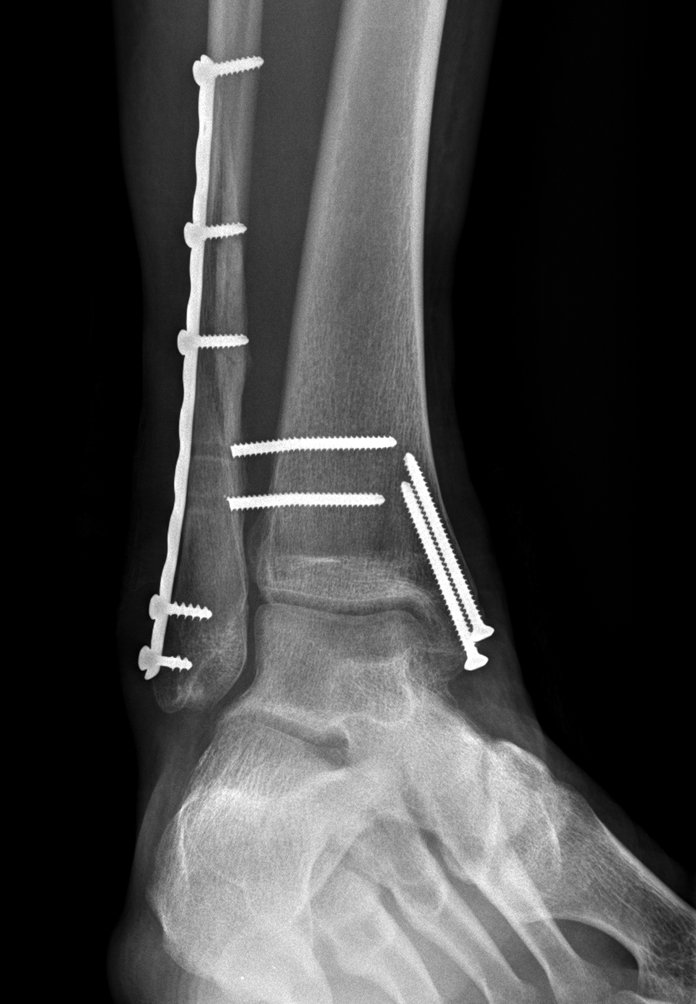

broken ankle Published February 15, 2012 at 696 × 1004 in TTT: The Magic 7 not miy x-rays but the same as mine